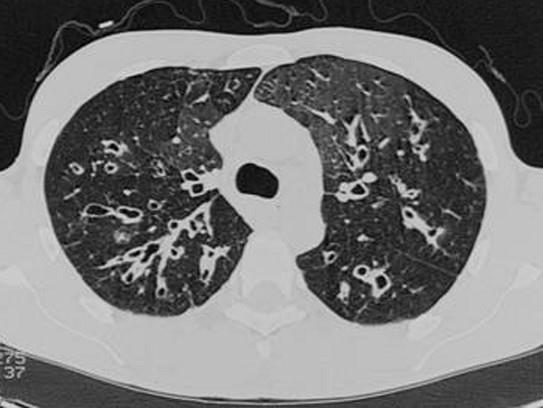

问题 年轻女性患者,X线胸片如图所示,该患者咳痰的特点为 ( )

选项 A、清亮的白色痰液 B、痰有臭味,甚至恶臭 C、黄绿色 D、清晨起床时诱发咳嗽、排痰 E、病人排痰量较多

答案 BCDE